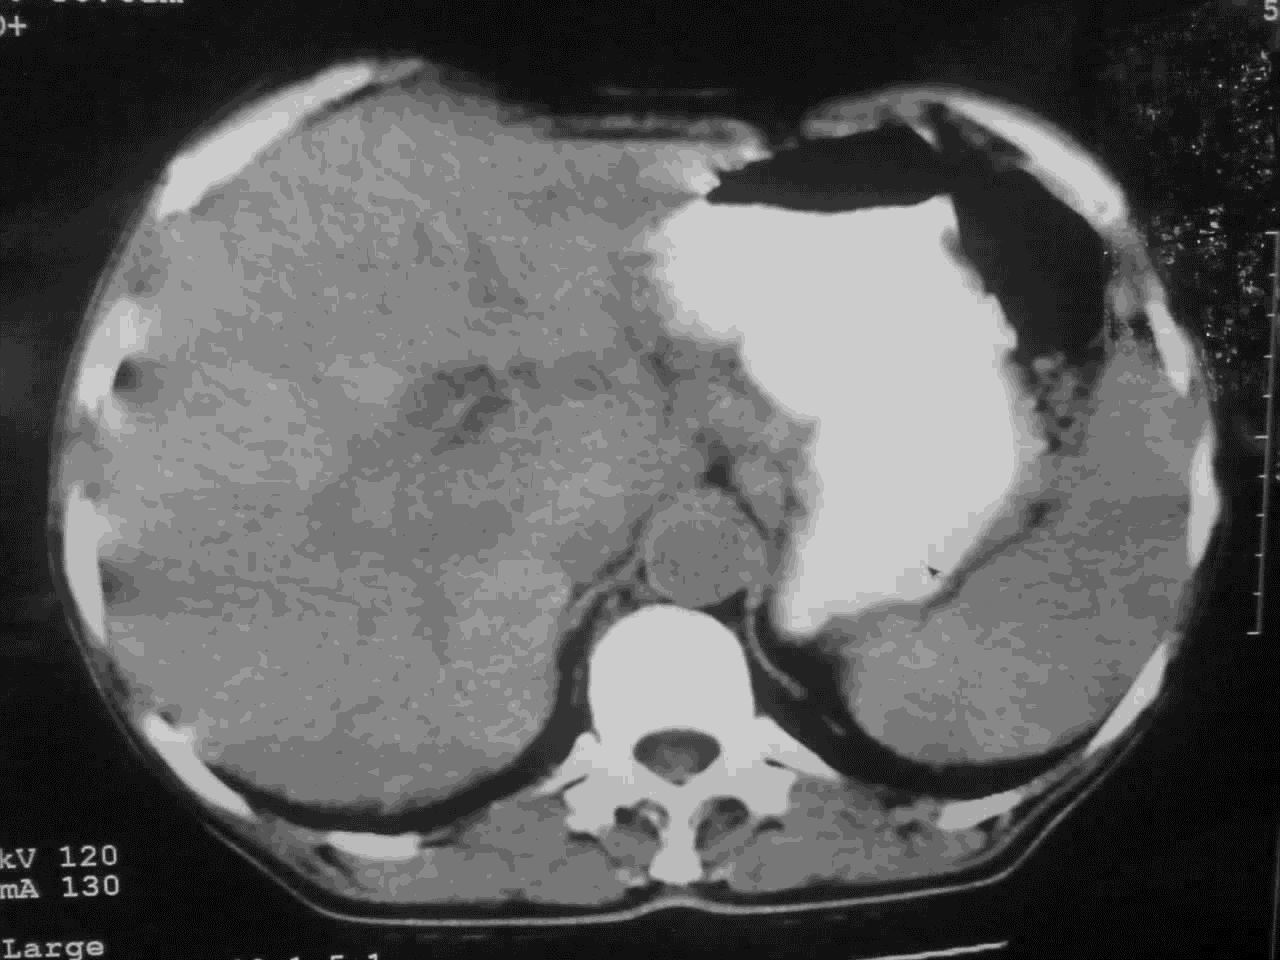

我这个考考大家眼力,看看是升结肠ca还是降结肠ca

下面的是4小时后的,

好象是横结肠占位肝转移,胰头占位?【伙计,您的片也真够意思】

伪影太多,考虑降结肠癌伴肝转移,胆囊炎

伪影太多,考虑升结肠癌伴肝转移,胆囊炎

考虑升结肠癌伴肝转移;胆囊炎。

结肠占位并肝及腹膜后淋巴结转移。

考虑升结肠癌伴肝转移;胆囊炎